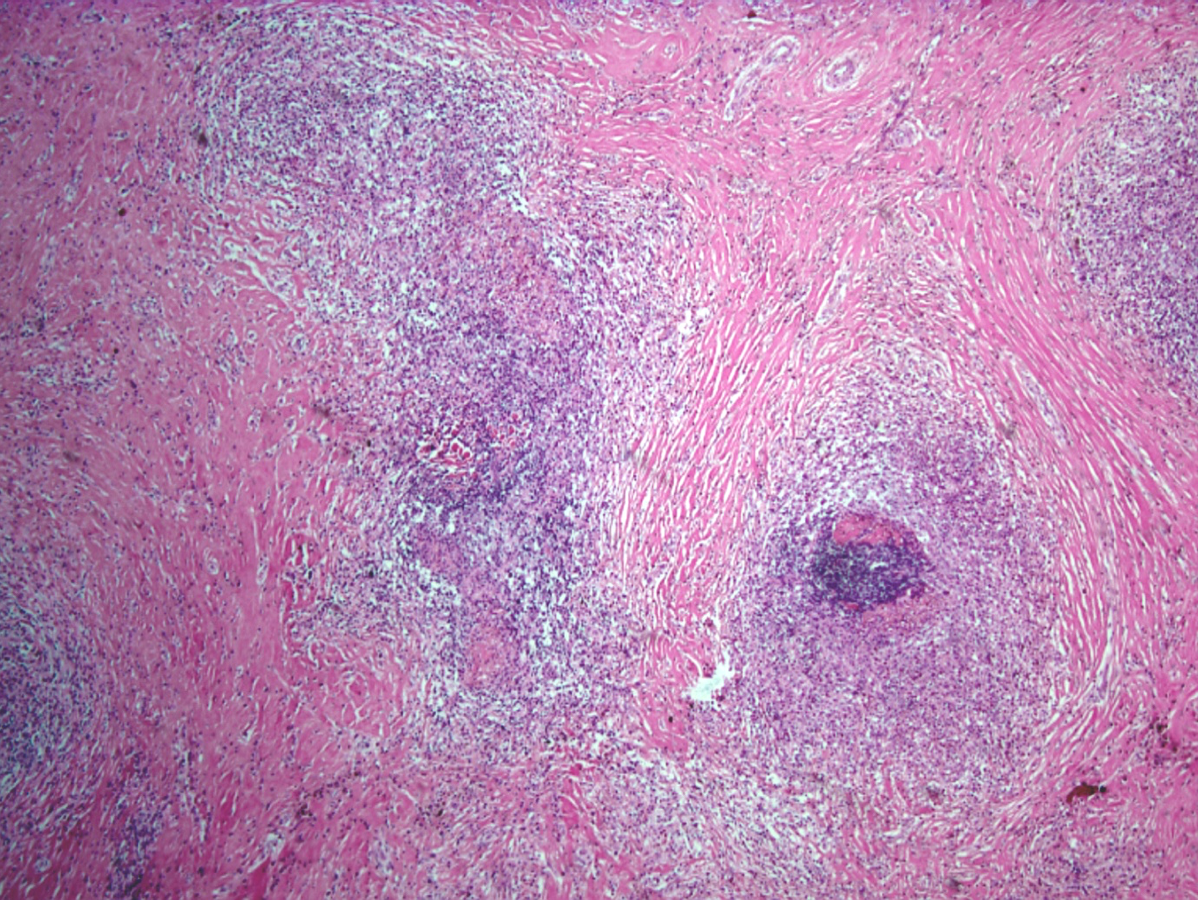

6.骨巨细胞瘤(bone giant-cell tumor)

是一种由较肥硕的梭形或椭圆形单核基质细胞和大量破骨细胞样多核巨细胞构成的侵袭性肿瘤,又称破骨细胞瘤(osteclastoma)。骨巨细胞瘤发病率较高,在我国仅次于骨软骨瘤和骨肉瘤而居骨肿瘤的第三位。绝大多数骨巨细胞瘤患者在20-40岁之间,15岁以下罕见,10岁以下极罕见。骨巨细胞瘤最常发生在长骨的骨端,常见于股骨下端、胫骨上端与橈骨下端,呈溶骨性。

肉眼观,瘤组织呈灰红色,质软而脆,常伴有出血、坏死、囊性变而呈多彩性,瘤体周围常有菲薄的骨壳。X线表现为肥皂泡样阴影。根据X线特点可将巨细胞瘤分为三类(Ⅰ级:安静型;Ⅱ级:活跃型;Ⅲ级:侵袭型)。安静型一般预后要好些。骨巨细胞瘤病灶内切除(刮除)后,约20-50%复发,5-10%发生恶性变,转变为纤维肉瘤和骨肉瘤。